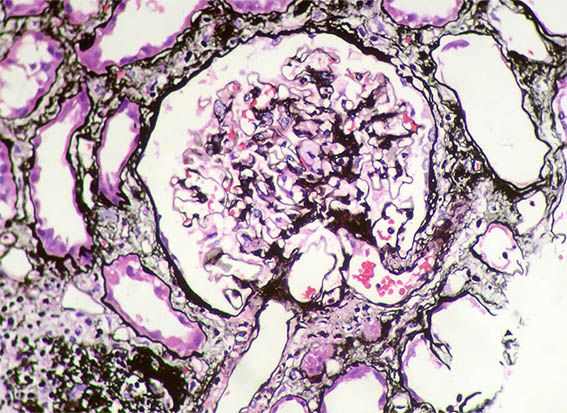

Figura 9. Plata-metenamina, X400.